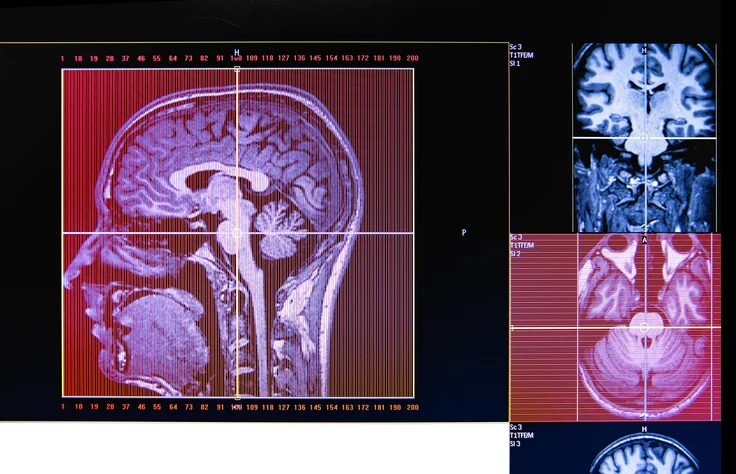

The brain contains billions of neurons (nerve cells) that create and receive electrical impulses. These electrical impulses are normal and allow neurons to communicate with one another. A seizure is a sudden surge of abnormal electrical activity in the brain. They occur when there is significant disruption of that normal electrical activity in the brain. The general symptoms of seizures may include changes in consciousness, sensation, movement, or behavior.